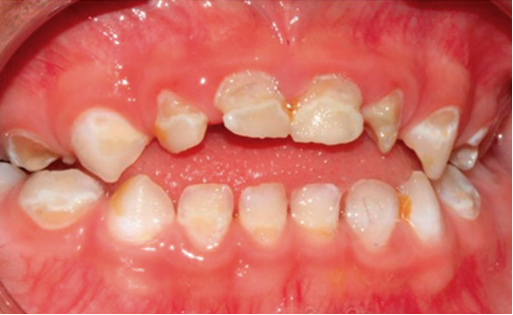

Se llevó a cabo la exploración extraoral y se logró apreciar una ligera asimetría facial, en las fotografías de perfil se ve la implantación de la oreja por debajo de lo normal (figura 1). Al hacer la exploración intraoral se encontraron sobre la superficie de todos los dientes manchas de color amarillento con descalcificaciones y lesiones cavitadas, al complementarse con la historia clínica y antecedentes patológicos, se determinó el diagnóstico de hipoplasia del esmalte generalizada (figura 2).

Figura 2. Examen clínico extraoral.